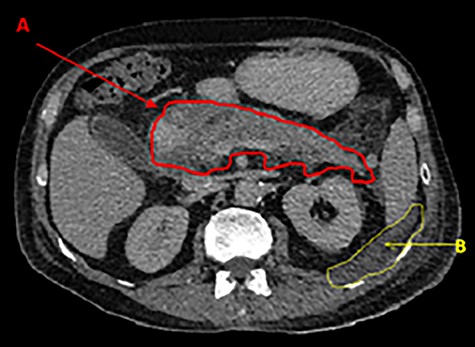

Contrast CT showing fluid tracking anteriorly into the left inguinal region (A).

A laparoscopic cholecystectomy and open hernia repair was planned. During surgery a pancreatic abscess was discovered with fluid tracking within the left inguinal canal. The left groin abscess was drained; however, the spermatic cord and cremaster were grossly implicated resulting in the need for a left orchidectomy. Post-operative CT scans showed a decrease in the inflammatory changes in the peripancreatic fat, in keeping with resolving pancreatitis.